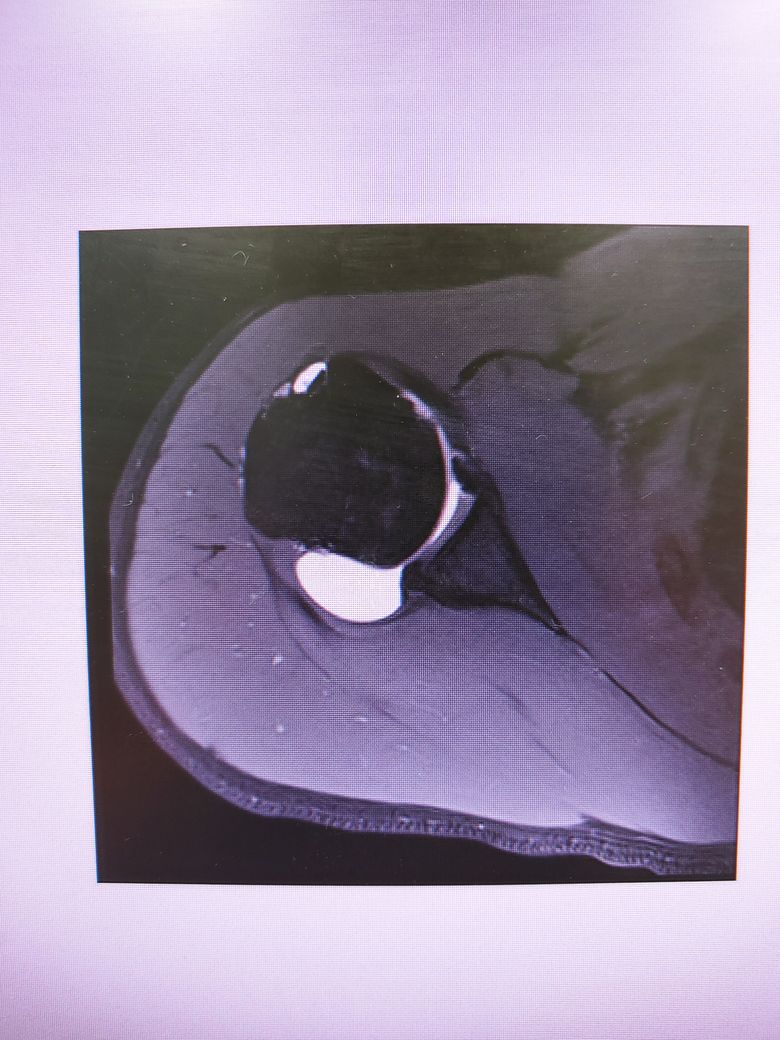

방카르트인지 한번 봐주시겠어요?

어깨를 움직일때 뒤쪽에 깊숙한 통증이있습니다.

염증인거 같긴한데 와순파열은 아닐지 걱정됩니다.

다음 사진에서 방카르트 소견이 있는 건지 봐주실 수 있을까요

• 2번 째 사진

MRI 4컷만 가지고는 방카트 병변을 명확하게 진단하기 어렵습니다.

현재 사진만으로는 방카트로 보이지는 않습니다.